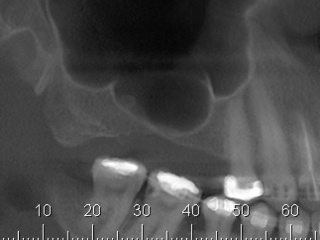

Enxerto de seio maxilar